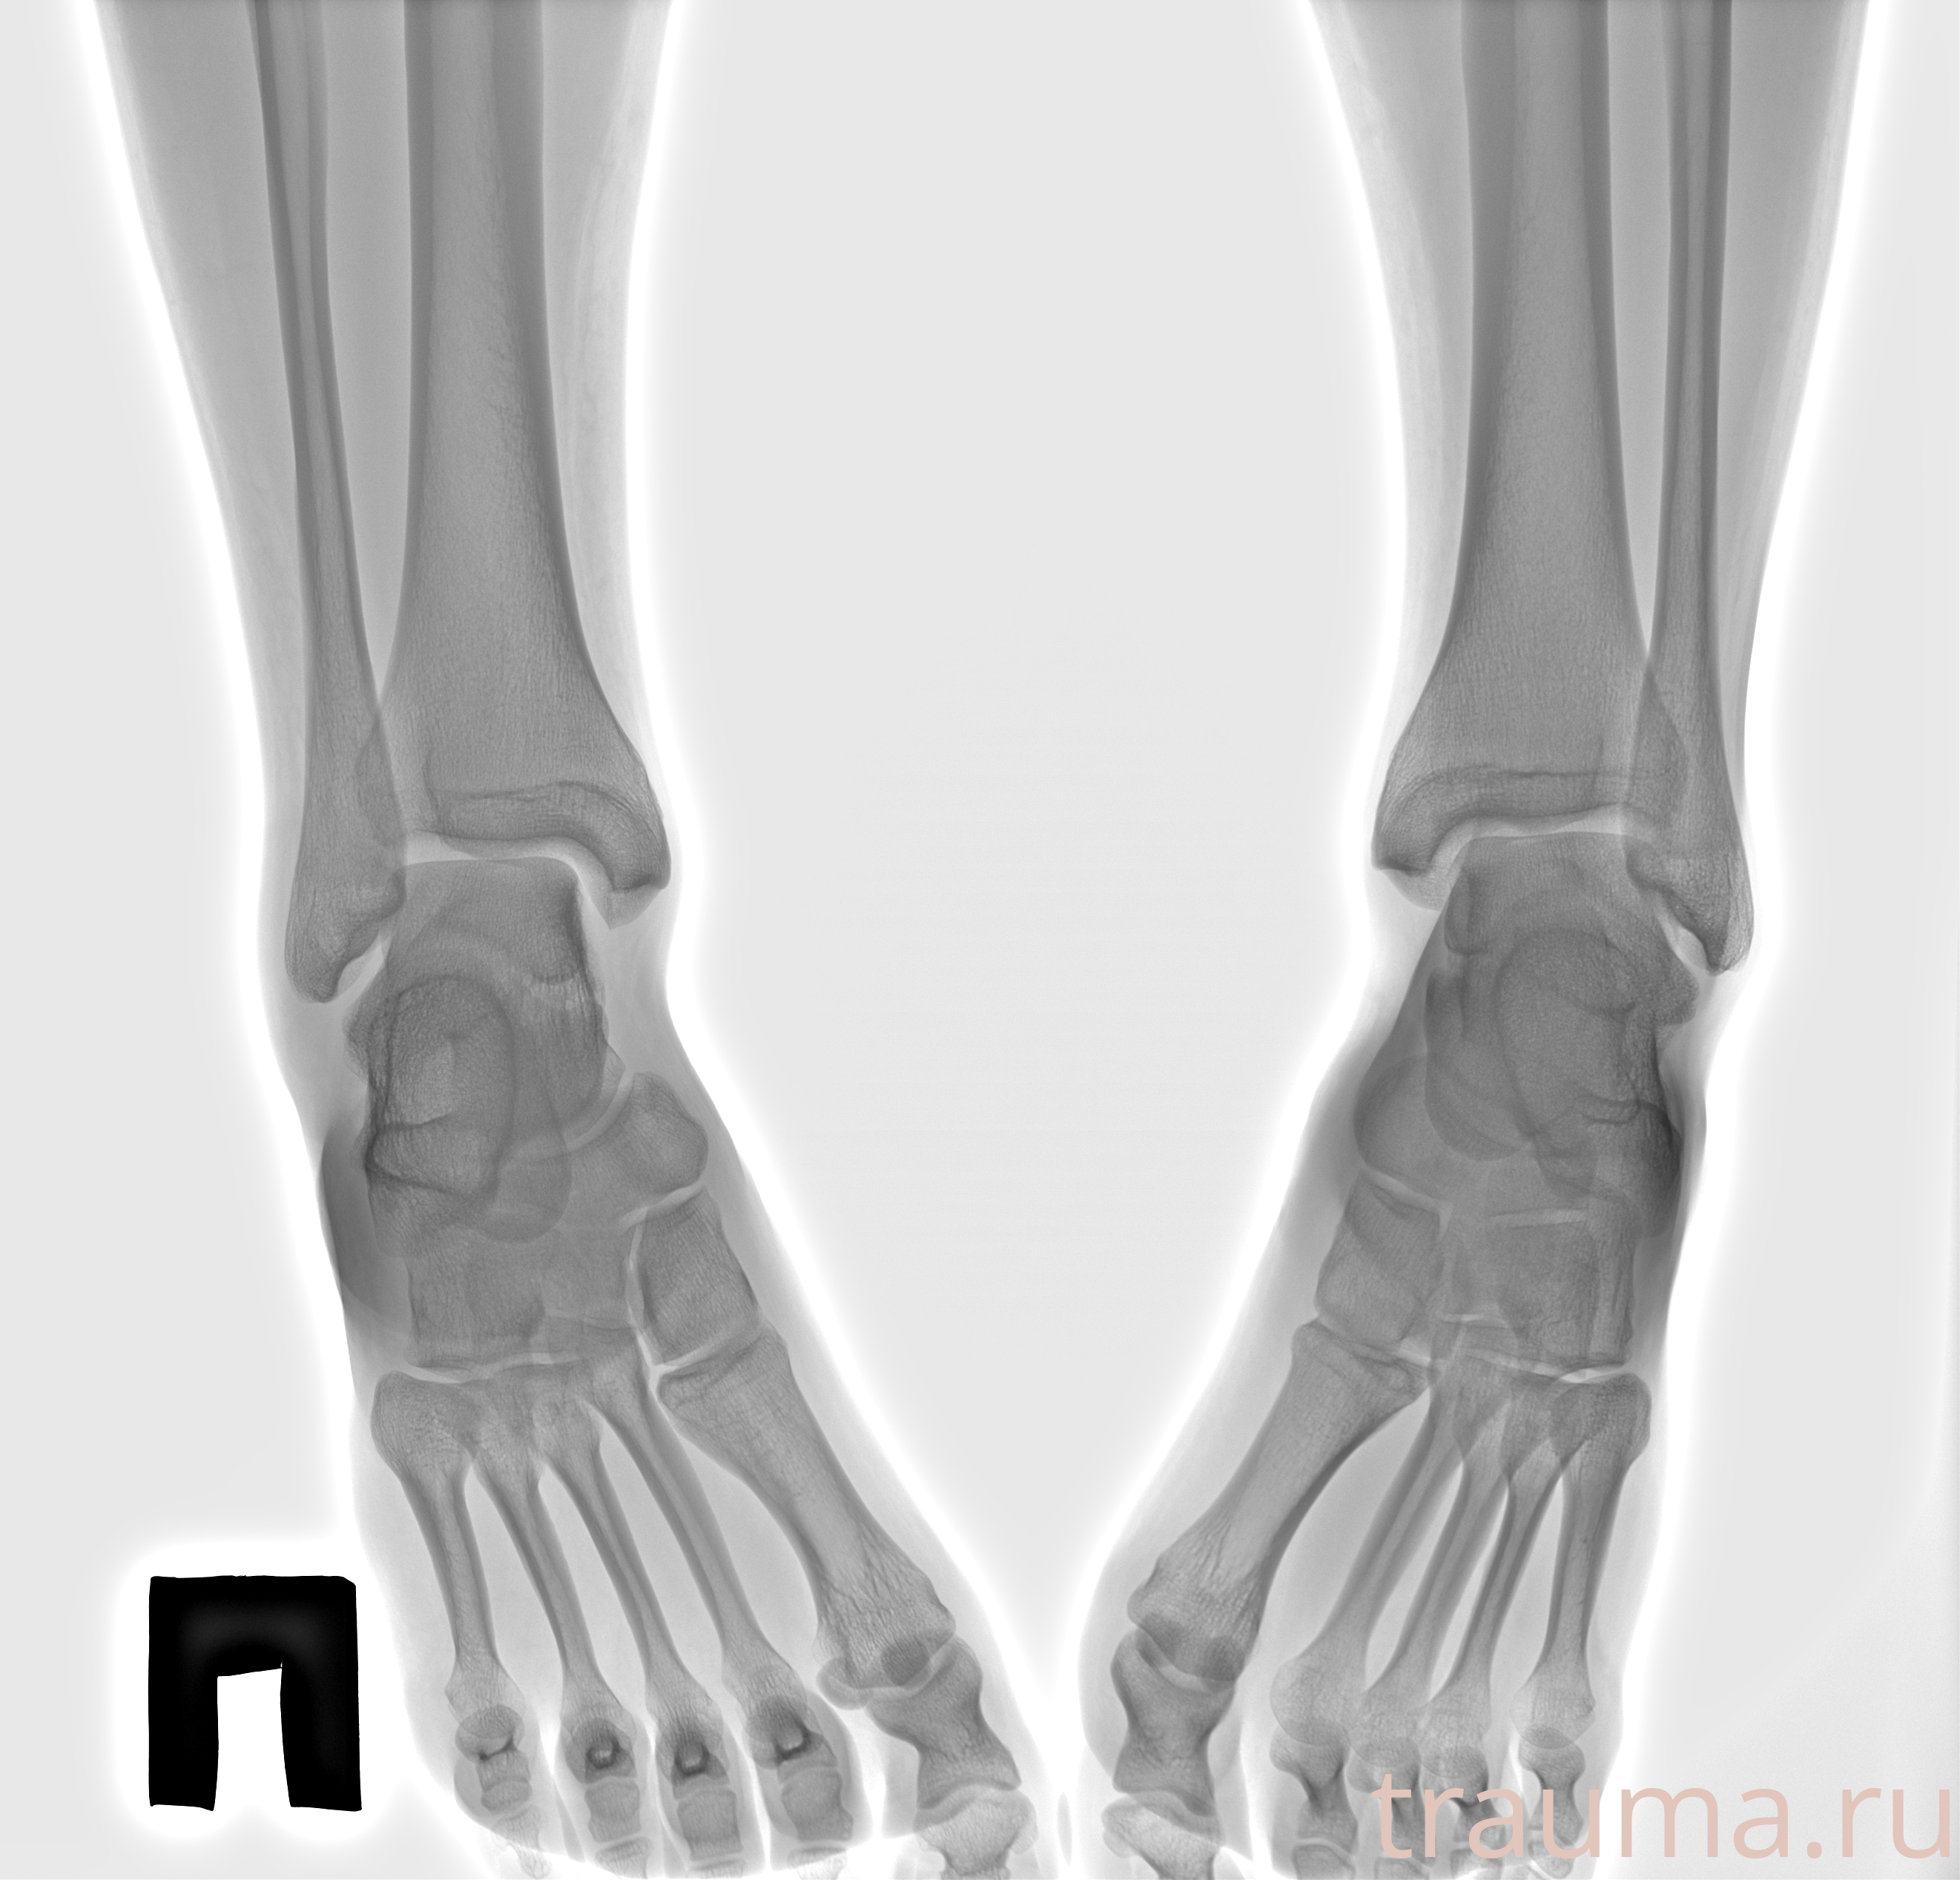

Рентген на дому: по вашему адресу приезжает врач-рентгенолог, травматолог-ортопед с мобильным рентгеновским аппаратом, проводит диагностику травмы или заболевания, делает необходимые рентгенограммы, дает рекомендации по дальнейшему лечению. Получить качественные снимки в домашних условиях возможно благодаря уникальной методике, разработанной МосРентген Центром для института  Склифосовского